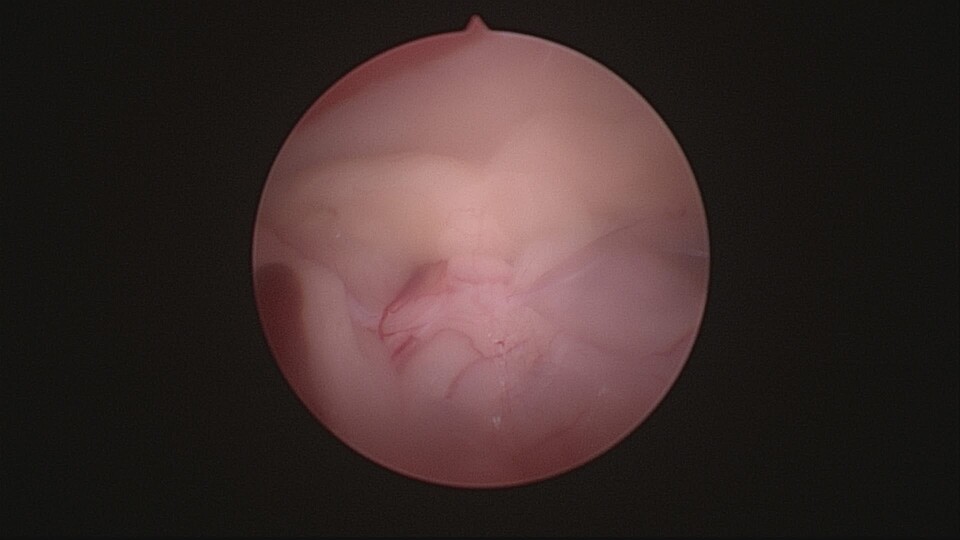

卵巢殘留症候群是指在進行卵巢子宮切除術(OHE)後,卻因卵巢組織未完全切除,導致體內仍有部分卵巢組織殘留,進而分泌性激素,引發類似發情的症狀。常見於狗與貓,可能會出現陰道分泌物、行為改變、乳腺腫脹等現象。

*卵巢組織切除不完全

*手術視野不佳或操作困難